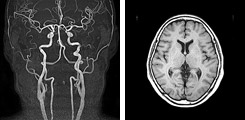

脳ドック:22,000円診(がんドック御利用の方:14,300円)

頭部(MRI・MRA)+頚部(MRA)

数種類の脳MRI(磁気共鳴画像)、2方向の脳血管MRA(磁気共鳴血管画像)を、モニター上で回転して立体的に観察し、異常がないか検査します。

もの忘れドック:27,500円(がんドック御利用の方:19,800円)

「もの忘れ」が単なるもの忘れなのか健康障害(脳血管障害・アルツハイマー病などの種々の病気)によるものなのかを早期発見するものです。

- 血圧測定

- もの忘れ相談プログラム

- MRI(頭部MRI・MRA・頚部MRA)検査

- VSRAD(海馬の萎縮の程度)

放射線科専門医による結果説明があります。(後日)